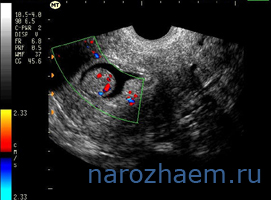

Исследование на УЗИ

УЗИ репродуктивных органов – позволяет увидеть слизистую матки и определить ее толщину, структуру (гладкая, имеет выросты и выпуклости и т.д.).